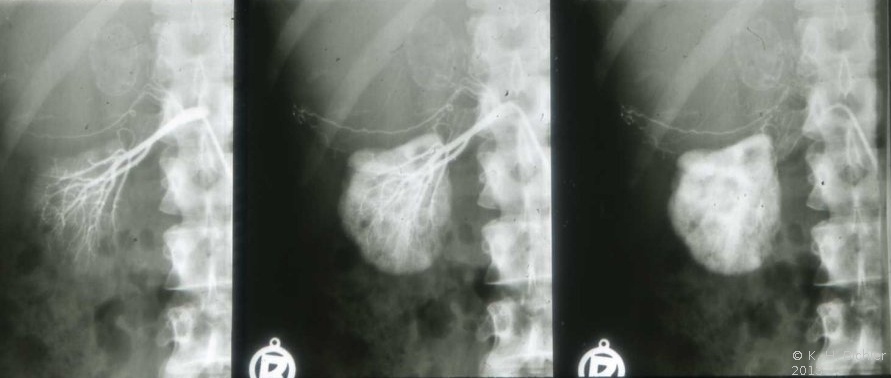

In einem weiteren Beispiel fand sich eine 8x10 cm große Nebennierenzyste, die in der Angiographie eine deutliche Abdrängung der rechten Niere zeigt